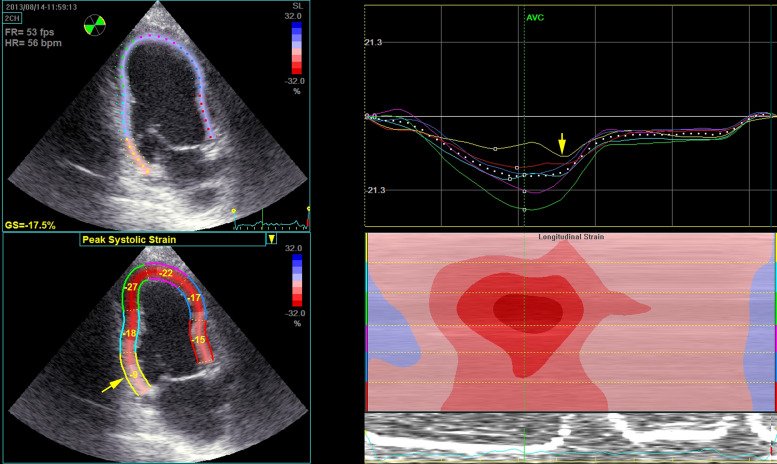

Modern echocardiography goes beyond just "looking."

With speckle-tracking strain imaging, we can measure myocardial deformation and detect subtle dysfunction, even when the wall motion still appears normal.

Sometimes strain detects ischemia earlier than the eye can. 2D speckle tracking on the apical two-chamber view showing a significant decrease of longitudinal strain within the basal inferior wall (yellow segment, arrow) with a clear post-systolic deformation (arrow) on the yellow curve from the same segment.

5/

One interesting marker is post-systolic shortening (PSS).

Normally, the myocardium finishes contracting before the aortic valve closes.

But ischemic segments may contract late, after systole.

That delayed contraction can be a clue to ischemia. Characteristic longitudinal strain patterns of a normal myocardial segment (dashed line) (A), a segment with decreased peak systolic strain and evidence of postsystolic shortening, most likely due to active contraction (B), and a segment with systolic lengthening and postsystolic shortening (C) most likely caused by passive recoil in a segment that is potentially scarred. AVC, aortic valve closure; ECG, electrocardiogram

Another powerful parameter is Global Longitudinal Strain (GLS).

Normal GLS is around −20%.

Less negative values often indicate impaired myocardial function and may hint at underlying coronary disease, even when ejection fraction looks normal. Image